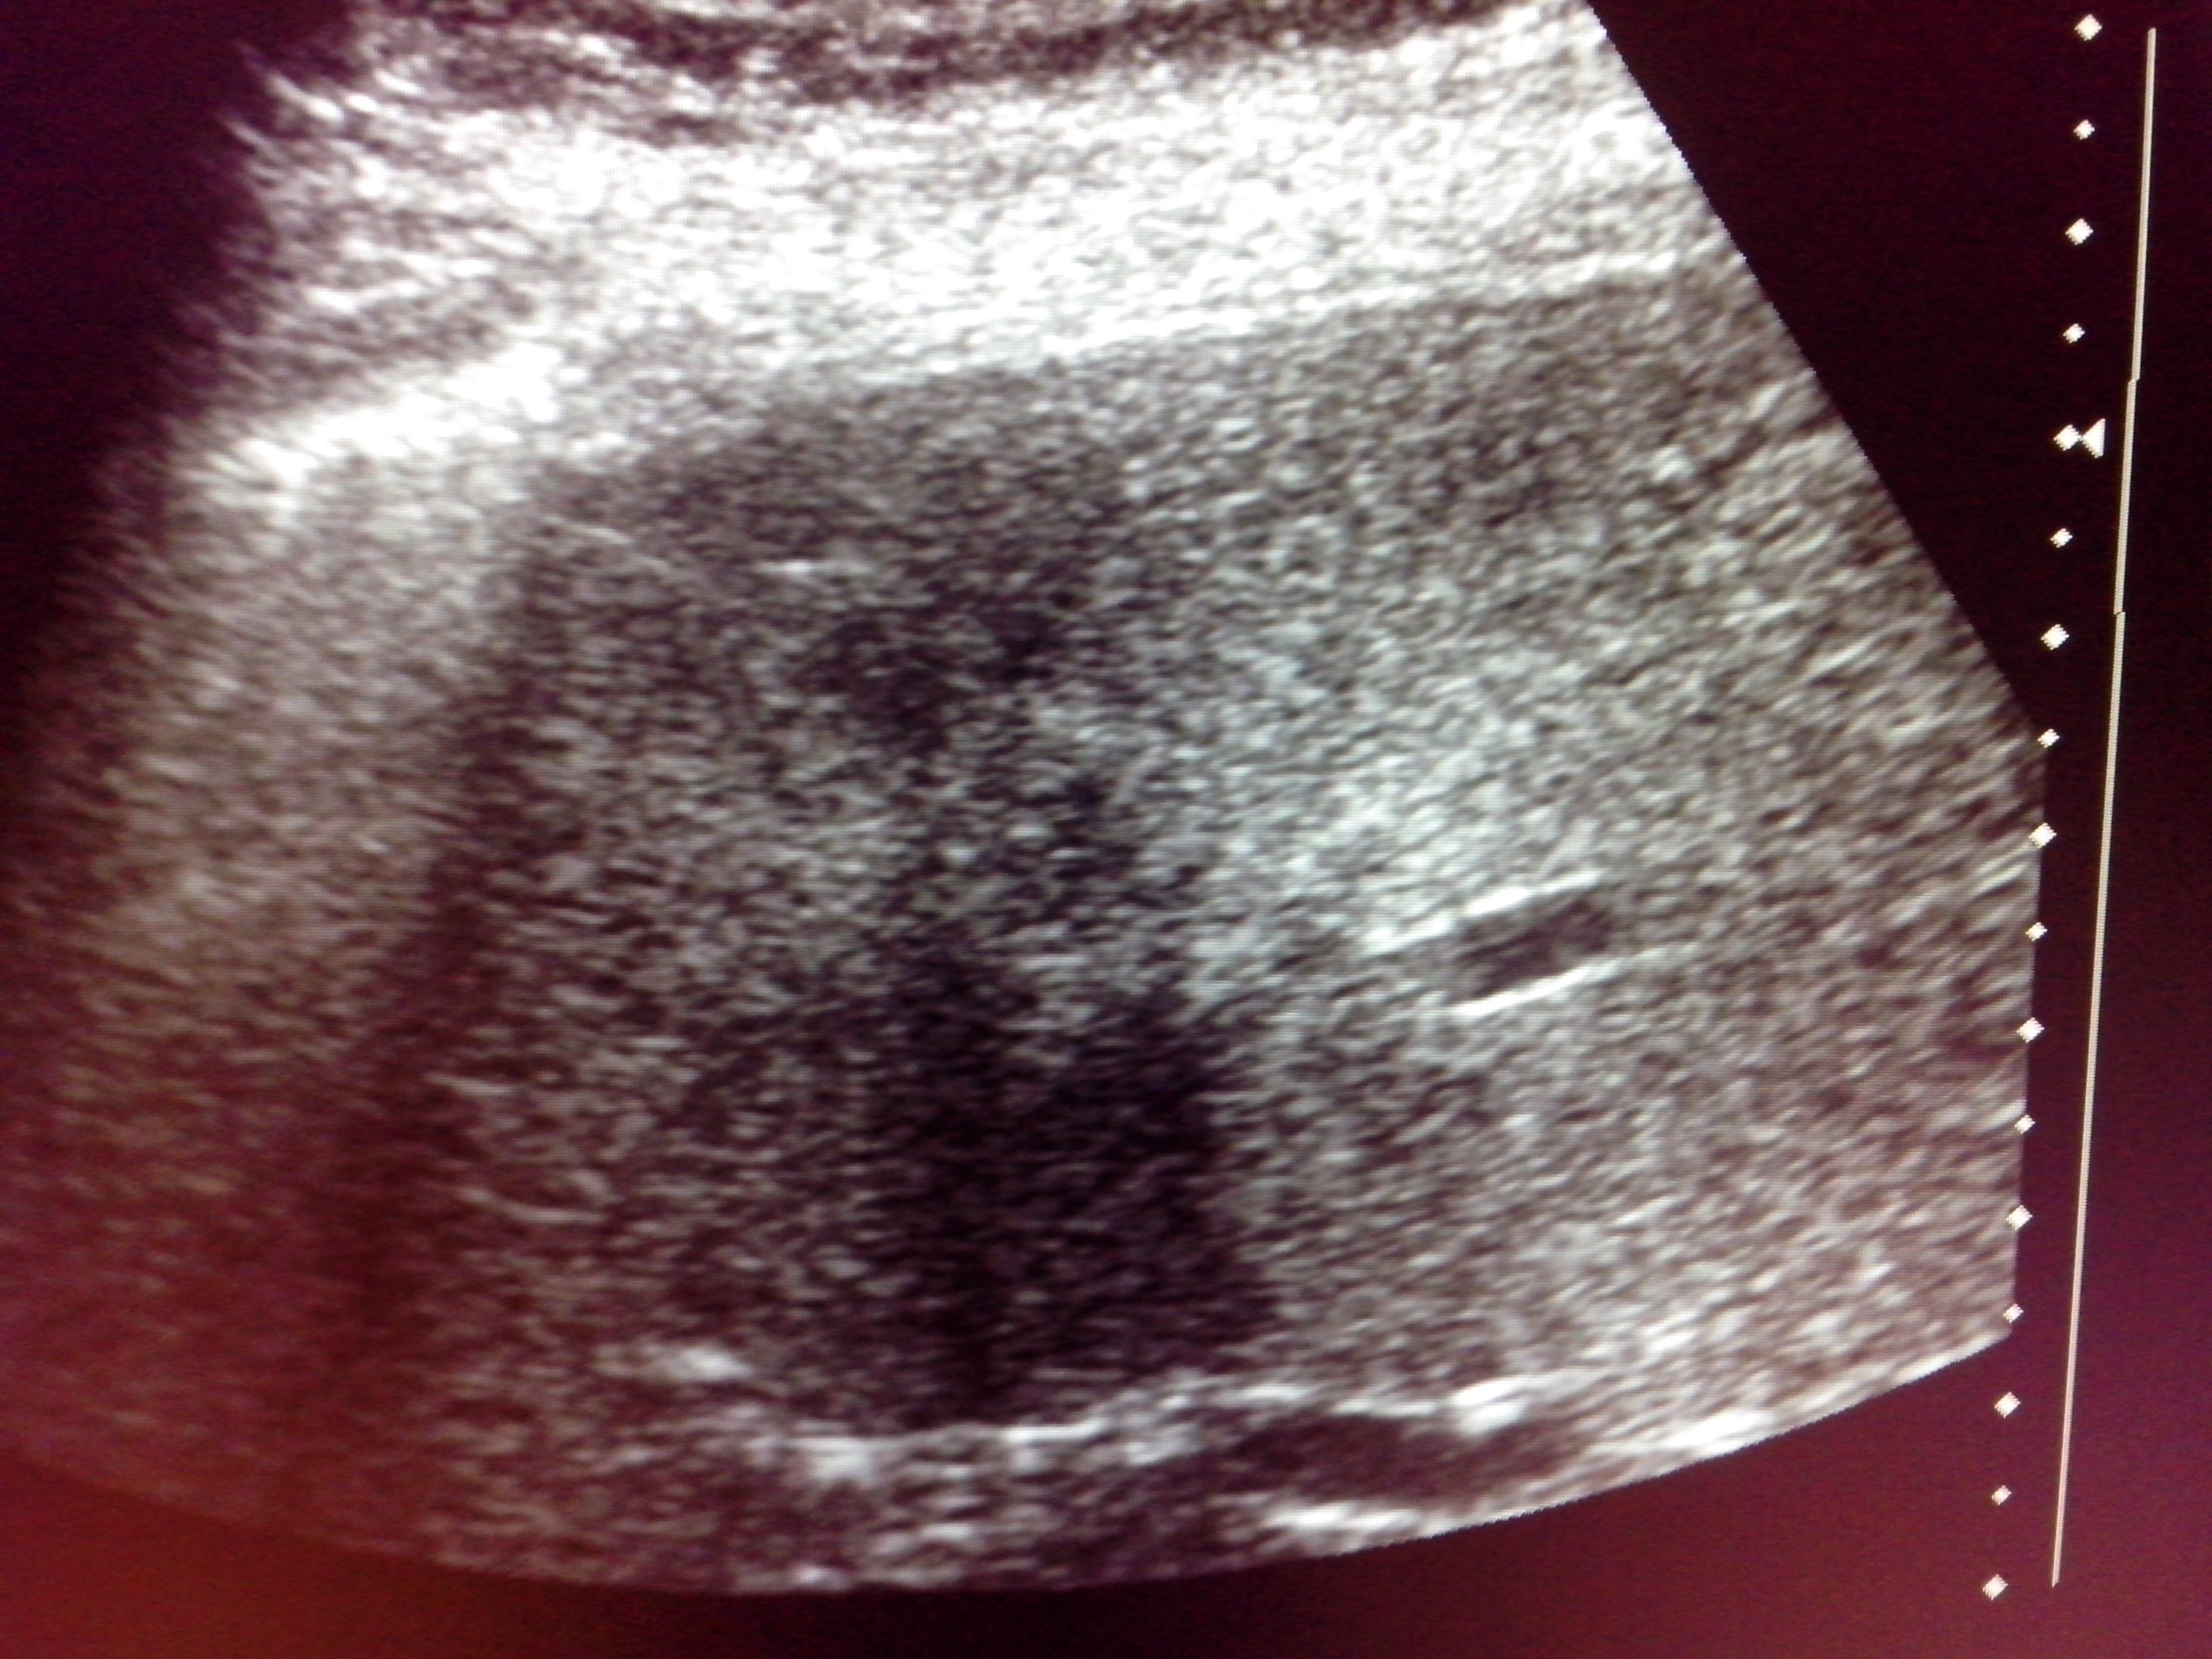

При госпитализации на УЗИ выявлено, что у пациента имеются четыре паразитарные кисты с живым эхинококом и одна киста - с признаками гибели паразита (отслоение оболочки):

Пациент оперирован под местной анестезией по принятой минимально инвазивной технологии в два этапа (за два операционных дня).

В первый день были оперированы четыре кисты, во второй - оставшаяся одна киста.